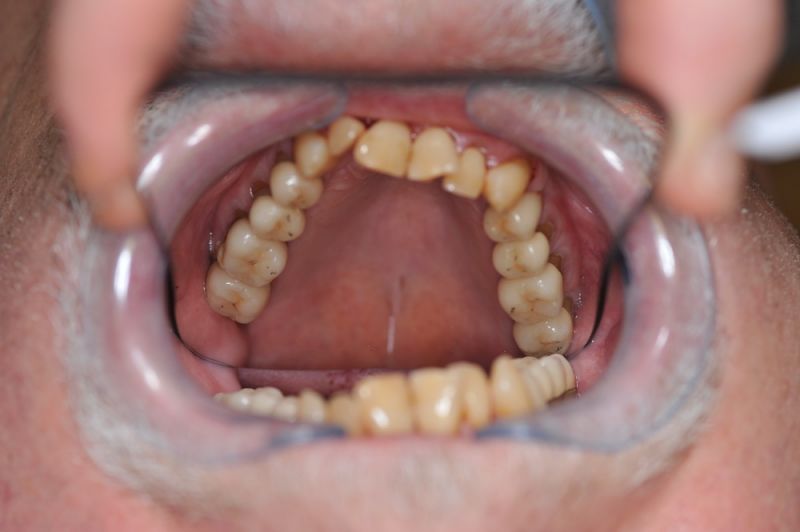

Der Patient erhält die beiden letzten Kronen zur Einstellung der dynamischen Okklusion.

Die funktionstherapeutische Behandlung ist damit abgeschlossen. Der Patient ist vollkommen beschwerdefrei. Beschwerdelevel: "0".

In diesem Fall möglich über die Herstellung von zwei Eckzahnkronen